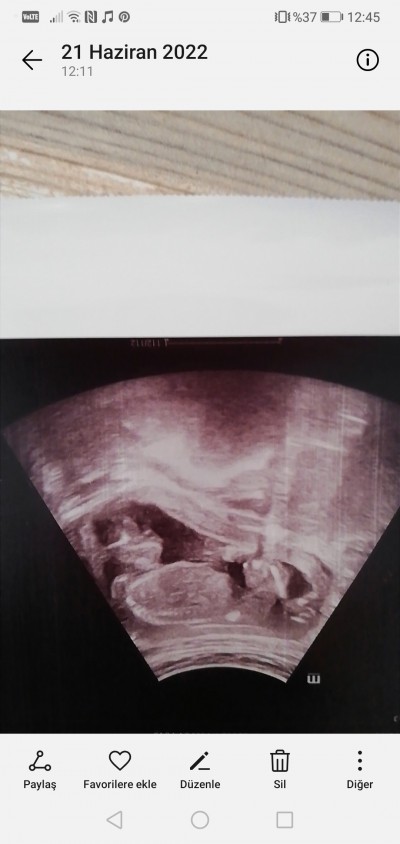

Kızlar s sizce cinsiyeti ney doktorum tahmin yaptı ama 1 ay dhaa bekleyelim dedi :)) biizmli bacakları üst üste yatıyor anası kılıklı hep böyle pozisyonu :D

Gebelik haftası 17